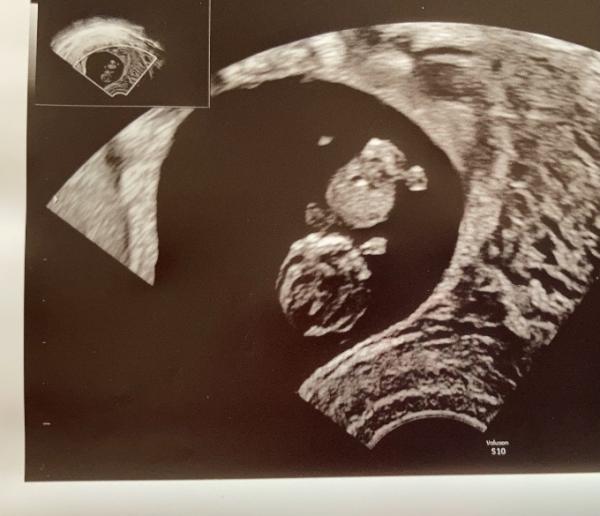

Ich stelle mich mal vor: Ich bin 25 Jahre alt, mein Partner ist 27 und wir sind seit 6 Jahren ein Paar. Geplant war die Schwangerschaft erst ab nächstes Frühjahr, der Krümel hatte es jedoch ein wenig eiliger Das Herzchen wummert ganz freudig und gewunken hat es beim Ultraschall auch schon fleißig. :) ET wurde bis jetzt auf den 12.07.21 festgelegt. Nächste Woche mach ich den Harmony Test, obwohl es dafür eigentlich keinen Grund gibt.... mein Freund ist sehr ängstlich und will das unbedingt. Zu uns gehört noch eine 1 1/2 jährige Hündin, die mir seit der Schwangerschaft nicht mehr von der Seite weicht und wann immer es geht mit meinem Bauch kuschelt. Seit der 6Ssw bin ich im Beschäftigungsverbot, da ich in einem Heim für auffällige Kinder arbeite. Dank Corona ist die Langeweile doch sehr groß tagsüber.. Ich freue mich über einen regen Austausch hier :)